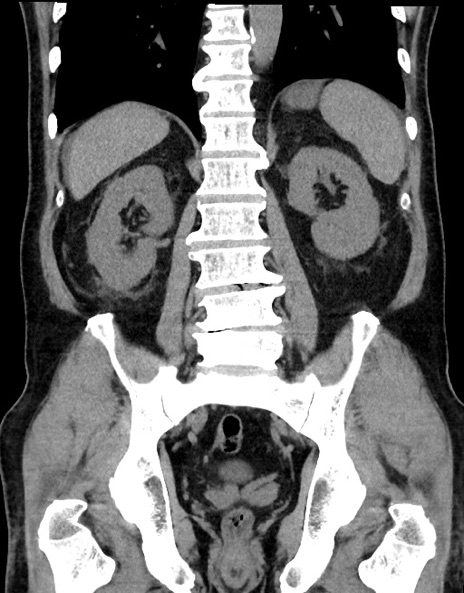

症例15(冠状断像)

【症例】70歳代男性

【主訴】腹痛

【現病歴】今朝から腹痛あり。全体的に痛い。特に左上の方。排ガスが今日はない。冷や汗が出る。

【既往歴】直腸癌術後

【身体所見】左側腹部〜上腹部に圧痛あり。腹膜刺激症状明らかなではない。軽度反跳痛。左下腹部に術後瘢痕あり。

【データ】WBC 7700、CRP 0.02